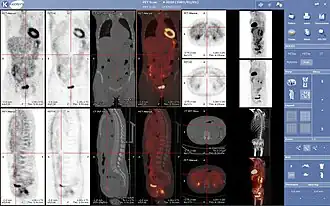

- 3D: ОФЭКТ — это трехмерный томографический метод, который использует данные гамма-камеры из многих проекций и может быть реконструирован в разных плоскостях. ПЭТ использует обнаружение совпадений для отображения функциональных процессов.

Проекция максимальной интенсивности (MIP) позитронно-эмиссионной томографии (ПЭТ) всего тела у женщины весом 79 кг после внутривенной инъекции 371 МБк 18F-FDG (за один час до измерения).

- Гибридные методы сканирования

Нормальная ПЭТ/КТ всего тела с ФДГ-18. ПЭТ/КТ всего тела обычно используется для выявления, определения стадии и последующего наблюдения за различными видами рака.

Аномальная ПЭТ/КТ всего тела с множественными метастазами рака. ПЭТ/КТ всего тела стала важным инструментом в оценке рака.